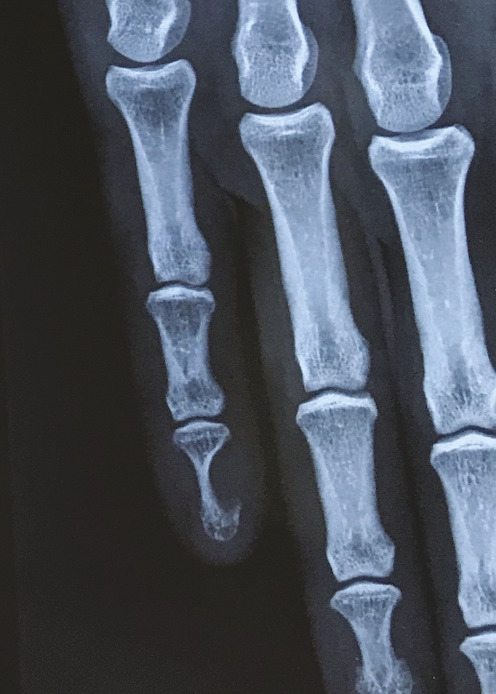

Des érosions osseuses peuvent être visibles sur les radiographies simples : un festonnage ou une empreinte de la phalange distale est mis en évidence chez 36 % des patients,15 jusqu’à de volumineuses lacunes osseuses (fig. 2).